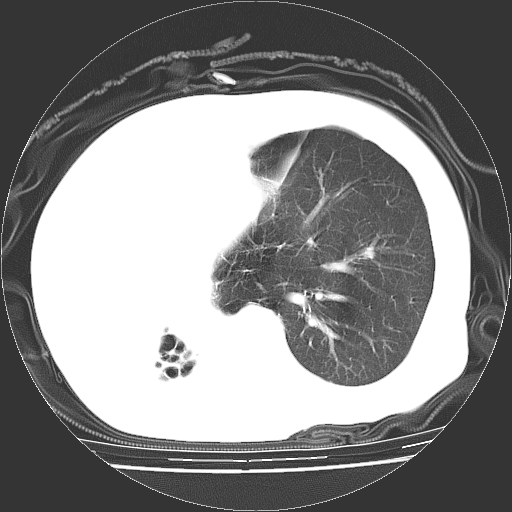

标题: CT23991:女,72岁,咳嗽、憋气一周。 [打印本页]

女,72岁,咳嗽、憋气一周,十年前曾患肺结核及胸膜结核。

1.右侧损毁肺伴胸膜钙化,2.左肺小结节灶,良性可能大,注意复查。3.肝脏左叶囊肿。4.先天性一侧肺不发育待出外(右侧胸廓无明显塌陷)。对比原片应该非常有帮助。